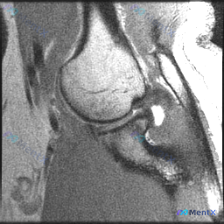

看到一份髋关节MRI的影像分析材料,原假设是盂唇病变,但提供的T1矢状位图像上没有发现明确的损伤征象。先放第一部分影像发现,大家第一反应怎么看?

看到一个髋部MRI病例资料,影像为冠状位T1加权序列。先看影像分析结果:显示股骨头、股骨颈、髋臼等结构正常,骨髓信号均匀,周围肌肉和肌腱信号均匀,关节间隙清晰,盂唇形态正常,未见明显异常病变信号。 但用户之前提示考虑“盂唇病变”,这是一个关键矛盾点。单看这张影像,有几个点值得讨论: 1. T1加权序...

整理了一例很有启发的髋关节MRI读片病例,分享一下我的分析思路,大家也可以一起讨论。 病例影像基础信息 这是一张髋关节冠状位T1加权MRI,我们先梳理所有可见的异常: 1. 股骨头区域:股骨头轮廓完整,关节间隙尚存,没有明显严重塌陷;但在股骨头前上方承重区,可见清晰的线样/带状低信号影,边界清楚,符...

最近看到一份单幅髋关节MRI T1加权冠状位图像的分析材料,用户的初始问题是关于“Labral pathology”(盂唇病变),但影像的核心客观发现似乎不太一致。先放分析内容里的关键信息,大家讨论一下: 影像表现: - 股骨头外形整体尚完整,前上方(负重区)皮质下见明显异常信号 - 股骨头、股骨颈...

看到一份髋关节MRI病例资料,原提问者提到“髋臼唇病变(Labral pathology)”。先放影像分析的核心发现: - 股骨头外上方承重区轮廓塌陷、变平,形态失真 - 股骨头内有特征性低信号带,将股骨头分为内侧正常区和外上侧异常区 - 软骨下骨板不连续,有“新月征”改变 - 关节间隙尚存,但有非...

看到一个单层面髋关节冠状位T1加权MRI的病例材料,患者想判断是否有盂唇病变。先放这张影像的观察信息和用户的问题,大家讨论下仅凭这张图能不能诊断盂唇病变? 基础信息: - 图像类型:髋关节冠状位T1加权MRI - 用户提问:是否有盂唇病变? 当前观察到的信息: - 骨性结构:股骨头、髋臼形态正常,关...

最近看到一个髋关节MRI病例,提供的是单帧T1冠状位影像,临床怀疑盂唇病变。但T1序列对软组织的分辨率有限,尤其是对盂唇这样的结构。大家基于这张影像,对盂唇病变的诊断有什么思路?或者有哪些其他的考虑方向?欢迎讨论!